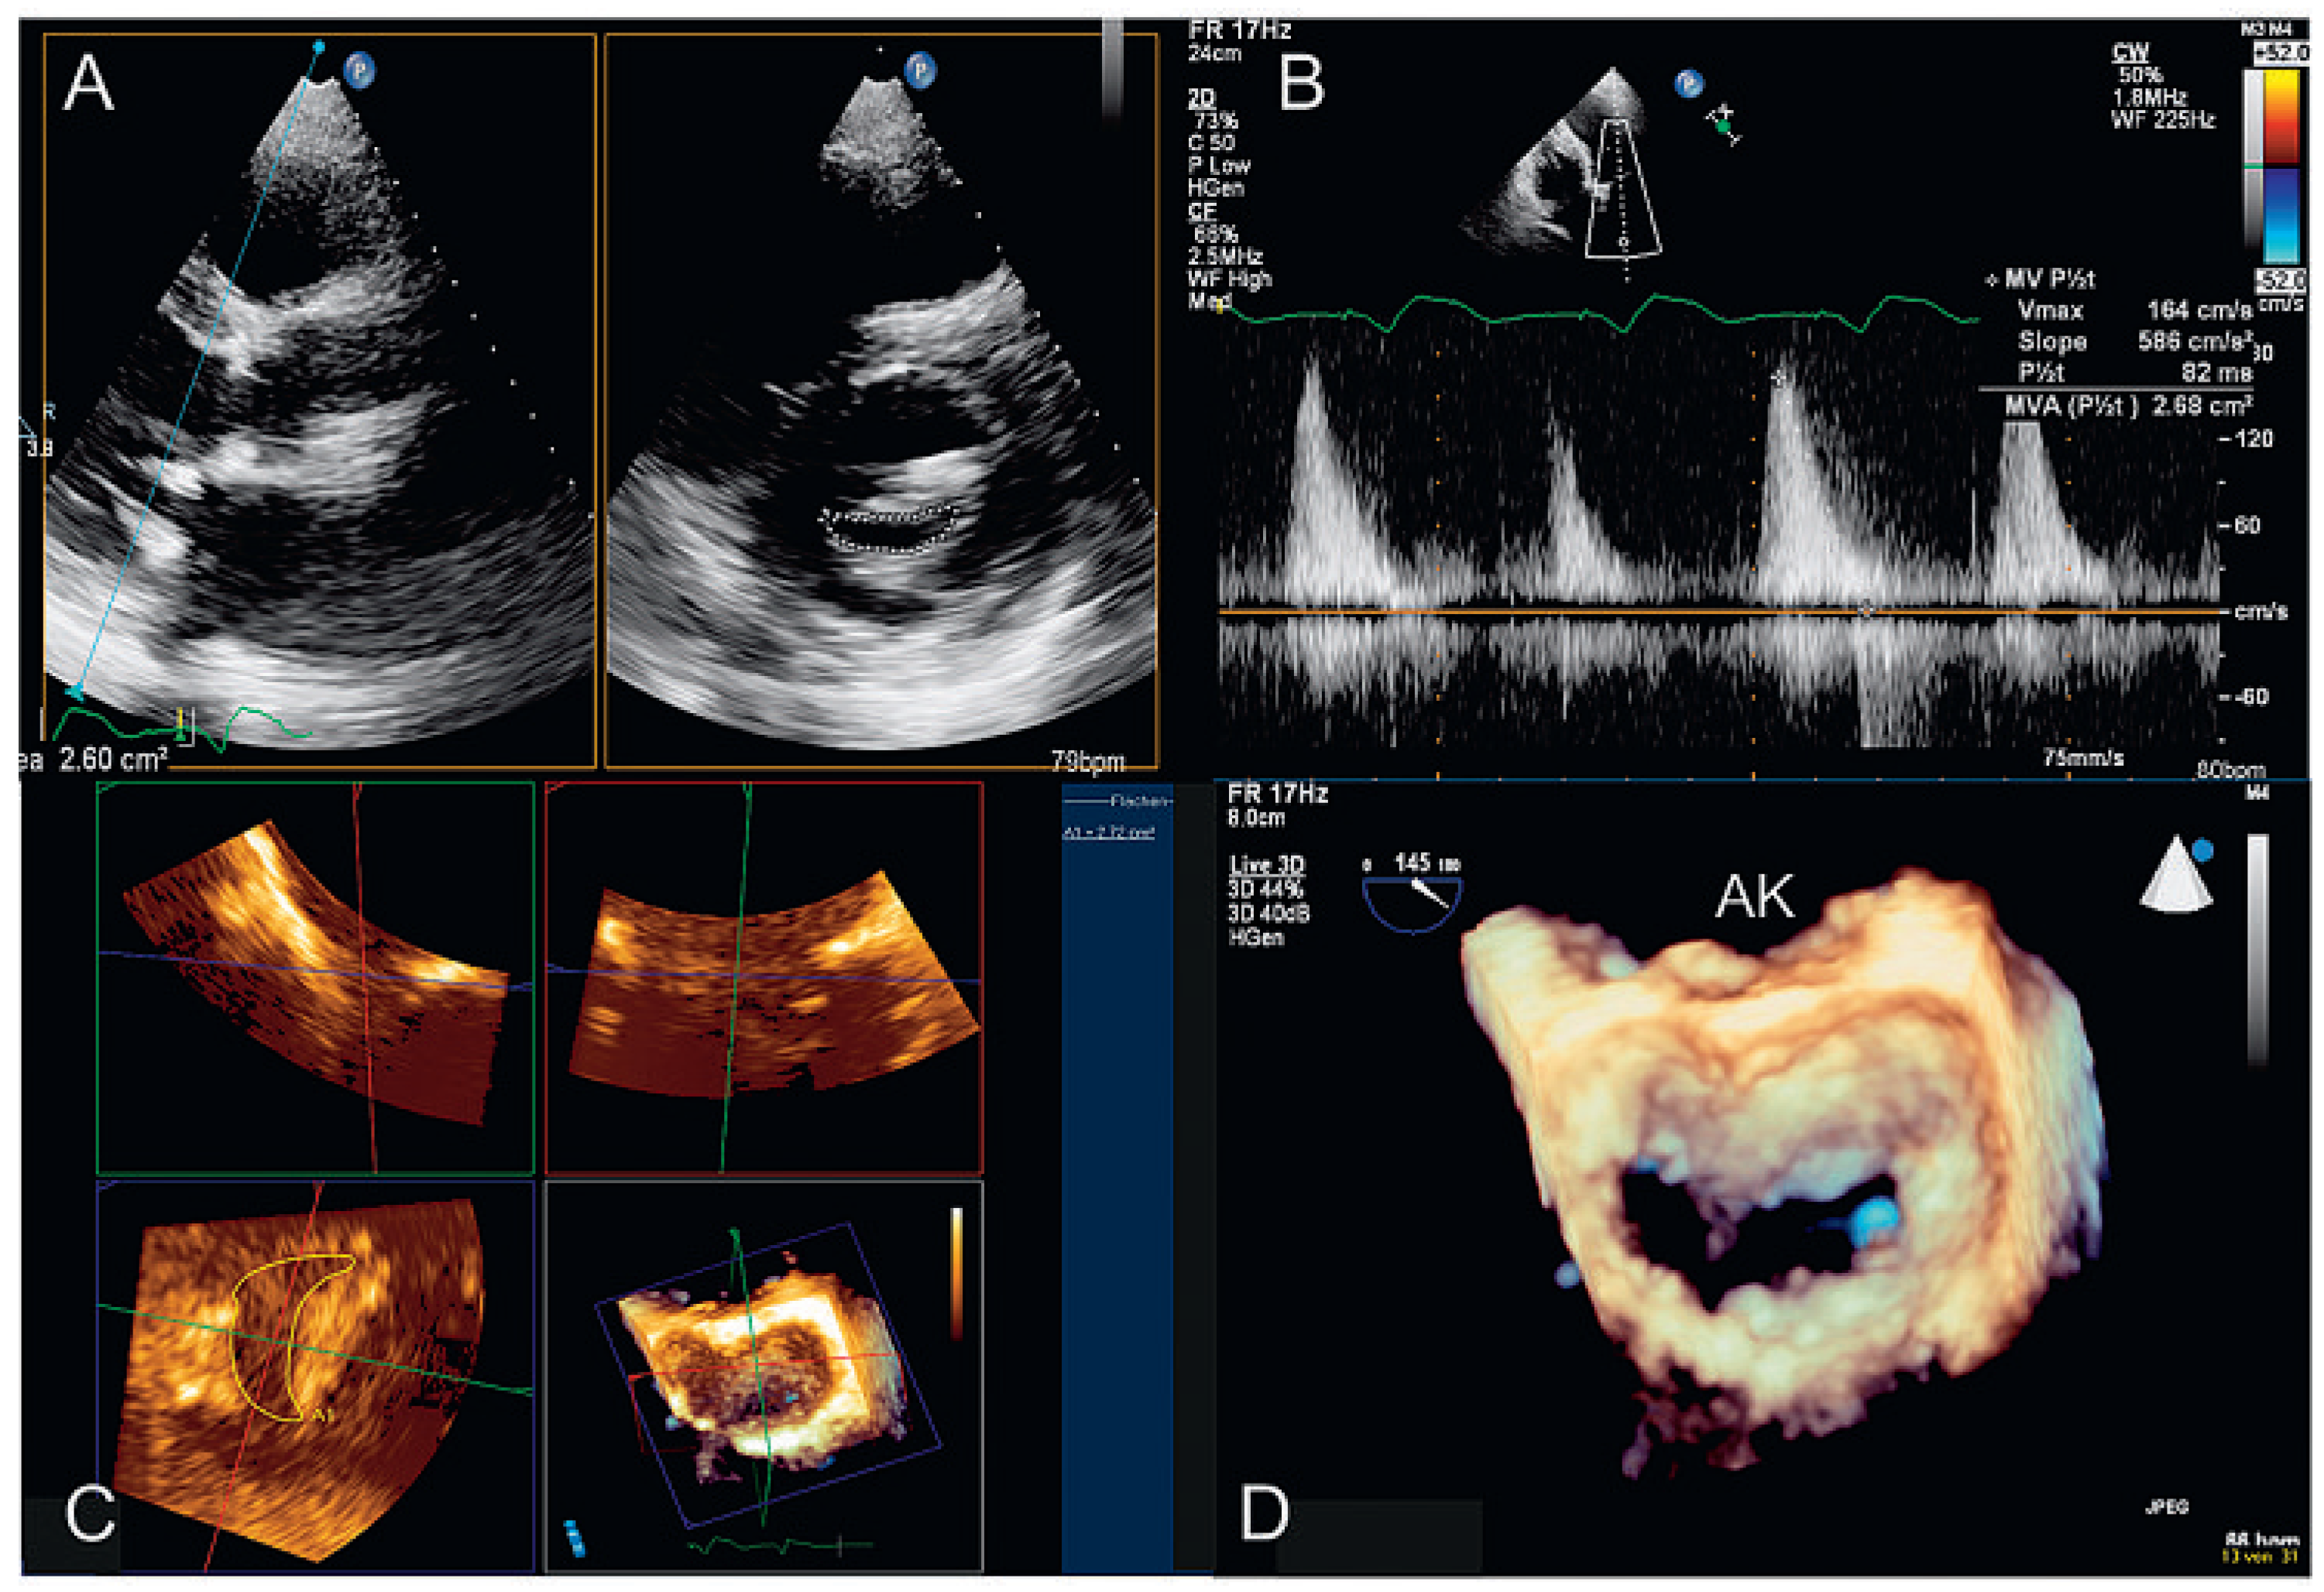

3D-TTE